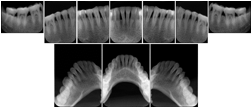

OO.1.2 Ophthalmology

1. A patient in rural Canada visits a general ophthalmologist and is found to have diabetic macular edema. The general ophthalmologist would like to discuss the case with a retina specialist before performing laser surgery. A fluorescein angiogram is done with multiple retinal images taken in a timed series after an intravenous injection. The images along with a Structured Display are shared via a Health Information Exchange with a retina specialist in Calgary, who opens them using his Ophthalmology EMR software and consults via phone with the general ophthalmologist. Both physicians view the images in the same layout so the retina specialist can provide accurate guidance for treating the patient.

2. A patient in rural Iowa visits his primary care physician for management of diabetes. Three non-mydriatic (patient's eyes are not dilated) photographs are taken of the back of each eye, and forwarded electronically along with a Structured Display to an ophthalmologist in Iowa City. The ophthalmologist reads the photos in an agreed upon layout so there is no mistake about what portion of which eye is being viewed. The ophthalmologist is able to tell the primary care physician that his patient does not need to come to Iowa City for face to face ophthalmologic care, but that there is a particular view of the left eye that should be photographed again in 6 months.

Ophthalmic Retinal Study Structured Display

Figure OO-3. Ophthalmic Retinal Study Structured Display